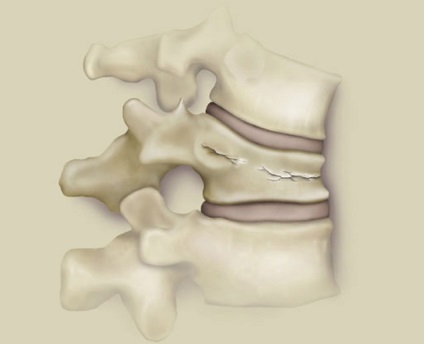

Componenta Unitate a coloanei vertebrale sunt vertebre si fractura de compresie este afectată acestora. Deoarece aceste oase la copii sunt mici, ele sunt adesea deteriorate într-o formă latentă, și lung rămân neobservate.

leziuni de compresie caracterizate printr-o puternică comprimare a coloanei vertebrale, astfel încât una sau mai multe vertebre iau forma de un fel de pană. Partea superioară a vertebrei deteriorat dincolo de marginea dreaptă, colțurile încep să fie presate în vertebre, situată sub prejudiciu, de la care începe să se rupă în jos structura.